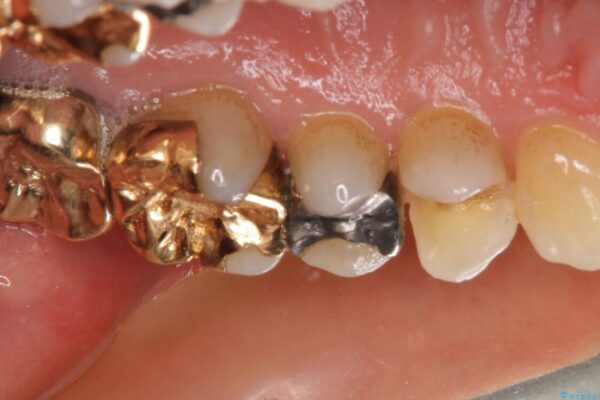

治療途中

• 外れてしまった銀歯 セラミックインレーで自然な仕上がりに 治療途中画像